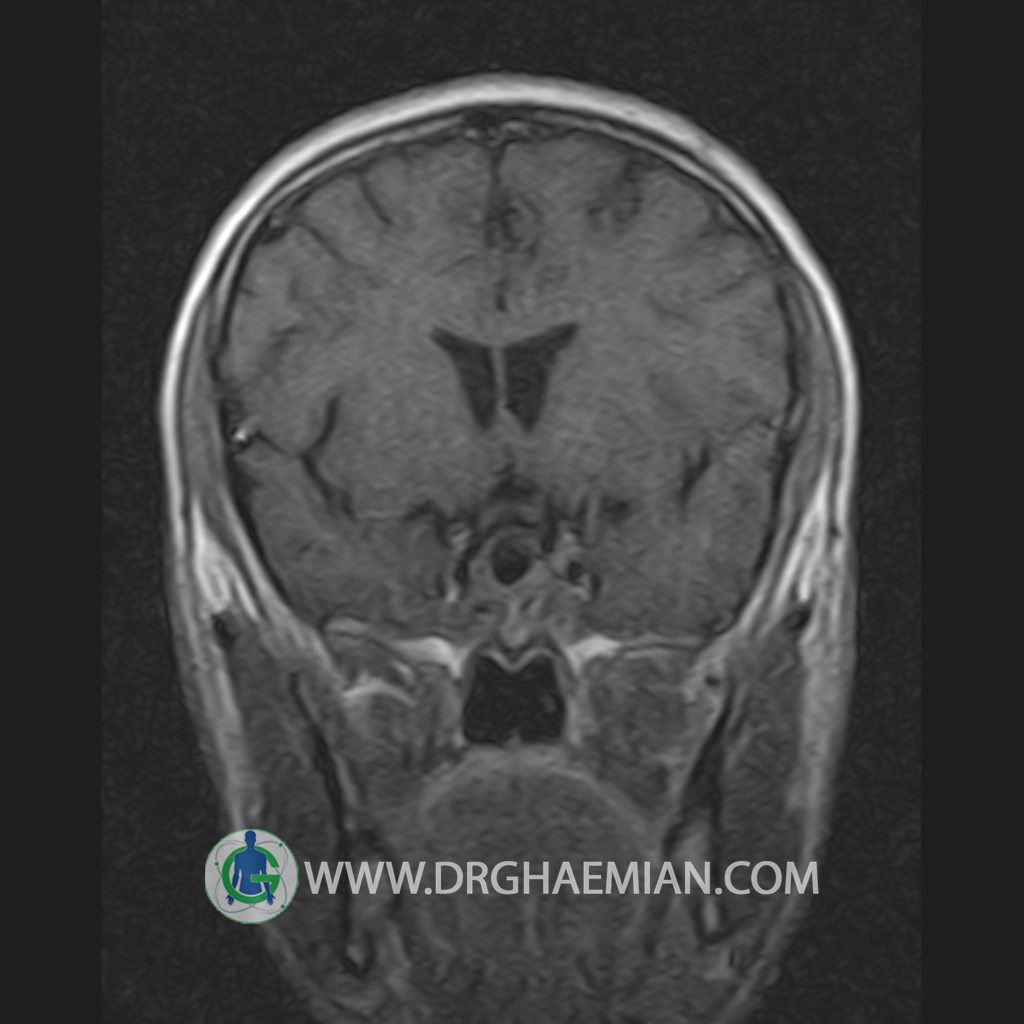

پزشکان اغلب از تصویربرداری ام آر آی برای تشخیص و درمان عارضه های پزشکی که فقط با استفاده از اشعه ایکس یا میدان مغناطیسی و امواج رادیویی قابل مشاهده است، استفاده می کنند. دستگاه ام آر آی تصاویر دقیق از ساختار های داخلی بدن ایجاد می کند. در این کیس یک میکروآدنوم در هیپوفیز بیمار مشاهده می شود.

HYPOPHYSIS MRI

(with and without contrast)

Technique: Axial , coronal T1 , Axial , coronal , sagittal T2 , Axial, coronal T1 post Gd & 64 dynamic thin coronal slices.

REPORT :

The infundibulum is centered and of normal size .

The optic chiasm and suprasellar spaces appear normal .

The cavernous sinus and imaged portions of the internal carotid artery and carotid siphon are unremarkable .

Evaluable portions of the neurocranium show no abnormalities .

The sphenoid sinus is clear and pneumatized .

Imaging of the hypothalamus after contrast medium administration was normal.

– Small hypoenhancing mass lesion ( 3 x 4 mm ) in posterior of pituitary stalk suggestive for micro adenoma

– Mucosal thickening in ethmoid & maxillary sinuses

is seen